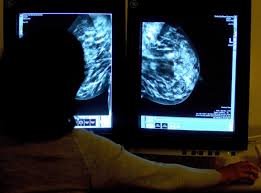

The average size of breast cancer, when found on mammograms, is 1.1 cm. A number of inherited mutated genes that can increase the likelihood of breast cancer have been identified. Breast cancers are sometimes detected when very small by the presence of microcalcifications in the breast. Place a pillow under your right shoulder and your right arm behind your head. Black women are the second most likely group to get breast cancer (124.8 per 100,000 women), followed by asian and pacific island women (102.9), hispanic (99.1), and american indian and alaska.

The average size of breast cancer, when found on mammograms, is 1.1 cm.

Ductal carcinoma in situ (dcis) invasive ductal carcinoma (idc) Increasing age is the most common risk factor for developing breast cancer, with 66% of breast cancer patients being diagnosed after the age of 55. Purpose we sought to determine how breast cancers that occur within 1 year after a normal mammogram are discovered. The earliest a tumor may be found on a mammogram is when it is between 0.2 cm and 0.3 cm in diameter. Tumor size is an important factor in breast cancer staging, and it can affect a person's treatment options and outlook. In fact, more than 80 percent of them end up being benign. The risk for breast cancer increases with age. Use light, medium, and firm pressure. An investigation into data from the icelandic cancer registry found that, out of 2011 unilateral breast cancer cases occurring from the years 1948 to 1987, 1139 of those cases were in the left breast, an excess of 13%. Place a pillow under your right shoulder and your right arm behind your head. These types of tumors are found in many other common cancers and form in glands or ducts that secrete fluid. Most types of breast cancers are adenocarcinomas of the breast. We surveyed women's primary care clinicians to assess how the interval breast cancers were found.

Ductal carcinoma in situ (dcis) invasive ductal carcinoma (idc) Some women will get breast cancer even without any other risk factors that they know of. The main factors that influence your risk include being a woman and getting older. Purpose we sought to determine how breast cancers that occur within 1 year after a normal mammogram are discovered. When lying down, the breast tissue spreads out evenly along the chest wall. A number of inherited mutated genes that can increase the likelihood of breast cancer have been identified. Invasive ductal carcinoma (idc) is the most common type of breast cancer. The ducts carry breast milk from the lobules, where it's made, to the nipple. The average size of breast cancer, when found on mammograms, is 1.1 cm. Tumor size is an important factor in breast cancer staging, and it can affect a person's treatment options and outlook. Breast cancer can occur anywhere in the breast, but the most common location is the upper, outer section of the breast. Decades after establishing the recognized standard for performing and teaching clinical and personal breast exams, the mammacare foundation wants women and others to be aware that most breast cancers are found by hand. The national cancer institute (nci) estimates that as of 2018, approximately 260,000 new cases of invasive breast cancer are diagnosed each year in the u.s.

The earliest a tumor may be found on a mammogram is when it is between 0.2 cm and 0.3 cm in diameter. Finding a lump in your breast can be frightening — but although breast cancer is the most common cancer found in women, most breast lumps are not cancer. In a small percentage of women, a painful breast lump turns out to be cancer. It can also occur in the armpit area, where there is more breast tissue (a.k.a. Using your left hand, move the pads of your fingers around your right breast gently covering the entire breast area and armpit.